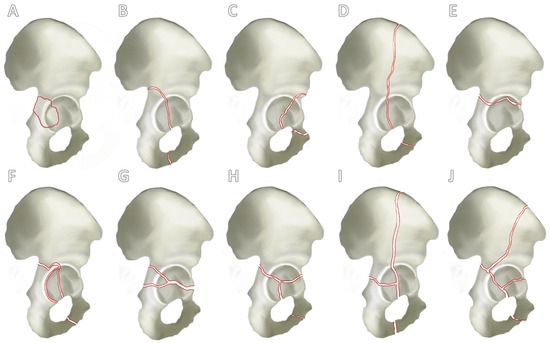

There are currently several classifications for the categorization of acetabular fractures, whereby it can be said that the classification according to Judet and Letournel from 1980 forms the standard in orthopedic and trauma surgery [21,22]. Judet and Letournel classified acetabular fractures into 10 types of fractures according to localization and fracture extension. These were divided into five simple fractures (Figure 2A–E) and a further five combined fractures of different structures of the acetabulum (Figure 2F–J).

Figure 2. Letournel’s classification. A differentiation is established between 5 simple fracture types and 5 combined fracture types. Simple fracture types (A–E) are the fracture of the posterior acetabular rim (A), posterior pillar (B), anterior acetabular rim (C), anterior pillar (D) and the transverse fracture (E). A further distinction can be seen between combined fracture types (F–J): fracture of the posterior pillar and posterior acetabular rim (F), transverse fracture and involvement of the posterior acetabular rim (G), T-fracture (H), anterior pillar with hemivertebral fracture (I) and the two-pillar fracture (J).